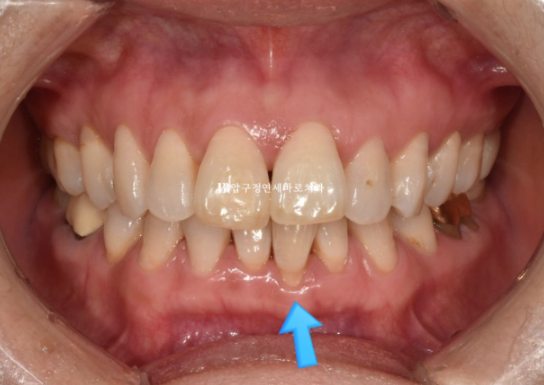

파란 화살표 부분은 잇몸이 주변치아에 비해 내려가있습니다

그 이유는 배열에서 가장 벗어난 치아여서 입니다.

제자리로 넣어주면 잇몸이 회복되기도 합니다.

배열이 가지런해졌고 소량의 치간삭제를 통해 블랙트라이앵글도 줄었습니다.

단 위 앞니 높낮이 단차가 있어서 이 부분을 추가장치에서 해결하기로 했습니다.